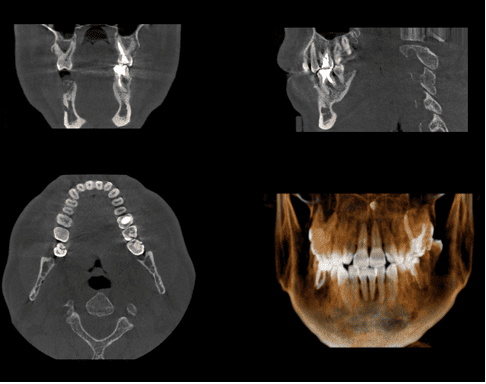

インプラント治療を安全に行うためには、事前検査はとても大切です。患者さんのあごの骨や周囲の組織の状態を詳細に検査して、より安全な治療計画を立てます。検査内容としては、歯科用CT撮影、口腔内写真、歯周病検査、模型検査などになります。

また、当院は先端の歯科用CTを導入し、精度の高いインプラント治療を行えるのが強みです。個室のオペ室をご用意して、外科手術に伴う感染リスクも最小限に抑えるなど、安心・安全なインプラント治療をご提供します。